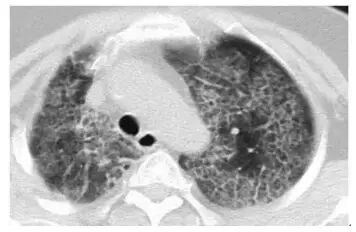

4. 肺淋巴管平滑肌肌瘤病

弥漫性的 GGO